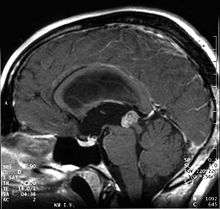

Papillary tumors of the pineal region (PTPR) were first described by A. Jouvet et al. in 2003 [1] and were introduced in the World Health Organization (WHO) classification of Central Nervous System (CNS) in 2007.[2] Papillary Tumors of the Pineal Region are located on the pineal gland which is located in the center of the brain. The pineal gland is located on roof of the diencephalon. It is a cone shaped structure dorsal to the midbrain tectum.[3] The tumor appears to be derived from the specialized ependymal cells of the subcommissural organ.[1][4][5] Papillary tumors of the central nervous system and particularly of the pineal region are very rare and so diagnosing them is extremely difficult.[6]